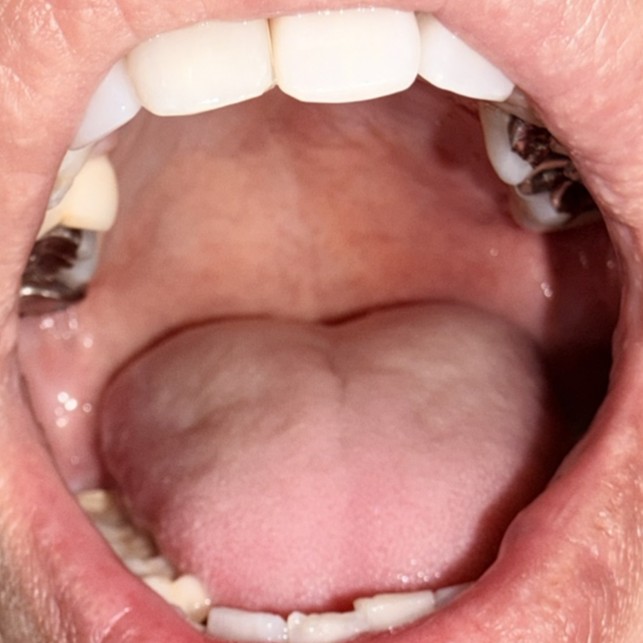

症例2 施術後1カ月経過